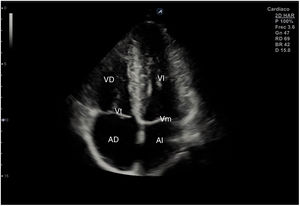

Para obtener los planos apicales la sonda se coloca sobre el latido cardiaco en el ápex, bajo la mamilla izquierda, a la altura del quinto espacio intercostal, con la marca dirigida a la izquierda del paciente y angulado en dirección al hombro derecho. Este plano, apical de 4 cámaras (fig. 8), muestra las 4 cavidades cardiacas y las válvulas auriculoventriculares vistas desde el ápex (fig. 9). En él, el plano del anillo tricuspídeo se sitúa más cerca del ápex que el mitral y el VD se ve más trabeculado. Es la vista de elección para medir la superficie de la AI, comparar el tamaño de ambos ventrículos y descartar la presencia de disfunción y/o dilatación ventricular. Angulando el transductor hacia anterior se obtiene el plano apical de 5 cámaras, que permite observar el tracto de salida del VI y valorar el flujo a través de la válvula aórtica (fig. 10); y al rotarlo 90° en sentido antihorario, el apical de 2 cámaras, que muestra las paredes anterior e inferior del VI (fig. 11).